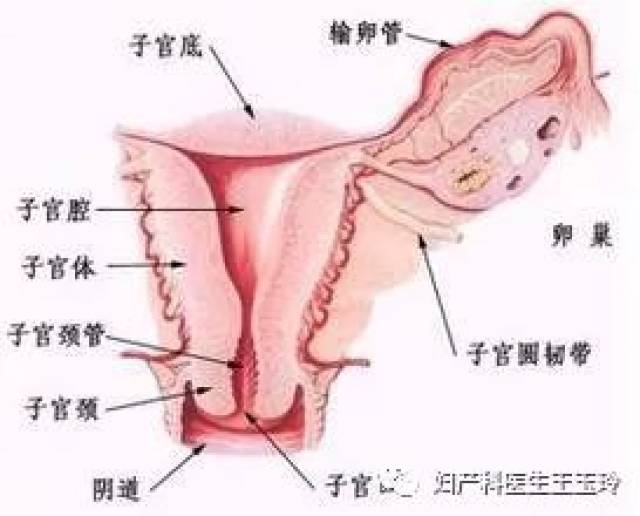

80 的人都感染过hpv,你会是宫颈癌的下个目标吗

为了抢救想当母亲的新冠病人,医护人员感染,花费超过500万美元